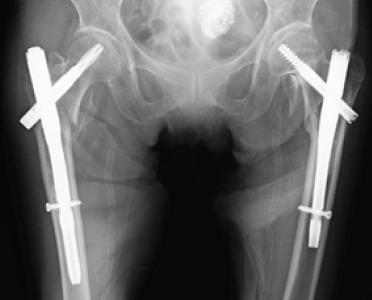

An 84-year-old woman presented with an atraumatic posterior hip dislocation that occurred 8 years after SFN fixation for an intertrochanteric hip fracture. She experienced an acute-onset left hip pain when standing up from a sitting position while bathing at a day care facility. We performed total hip arthroplasty (THA) with a dual mobility system. During the post-operative THA evaluation, the combined anteversion angle was within the optimum range of 57. However, the dislocation recurred after the THA. During the revision THA, a dual mobility system was used to moderately extend the stem neck. Measures were adopted to strain the posterior soft tissues of the hip joint. We speculated that the posterior hip joint capsule ruptured because the support of the posterior hip joint was weak after the intertrochanteric hip fracture. At the final follow-up visit at 6 months after the operation, the hip joint pain had disappeared, and her activities of daily living recovered to almost the same level as her preinjury activities.

一名84岁女性,在因股骨转子间髋部骨折接受SFN固定8年后出现非创伤性后髋关节脱位。她在日间护理机构洗澡后从坐姿起身时突发左髋疼痛。我们采用双动系统进行了全髋关节置换术(THA)。在术后THA评估中,联合前倾角在57°的最佳范围内。然而,THA术后脱位复发。在翻修THA时,使用双动系统适度延长柄颈。采取措施拉紧髋关节后部软组织。我们推测,由于股骨转子间髋部骨折后髋关节后部支撑薄弱,导致髋关节后关节囊破裂。术后6个月的最后一次随访时,髋关节疼痛消失,她的日常生活活动恢复到几乎与受伤前相同的水平。